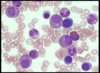

Identify the smear.

Identify the stain.

Bone marrow aspirate.

Giemsa or Wright stain.

Outline the stages of erythropoiesis shown here.

- myeloid precursor

- proerythroblast (aka pronormoblast)

- basophilic erythroblast/normoblast

- polychromatic erythroblast/normoblast

- orthochromatic erythroblast/normoblast

- reticulocyte (aka polychromatic erythrocyte)

- erythrocyte